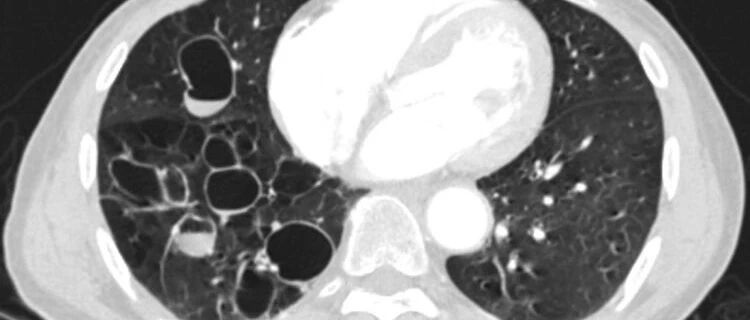

患者47岁,咳嗽咳痰,你的诊断是什么?│以影识病

来源:医脉通呼吸频道

时间:2020-08-22